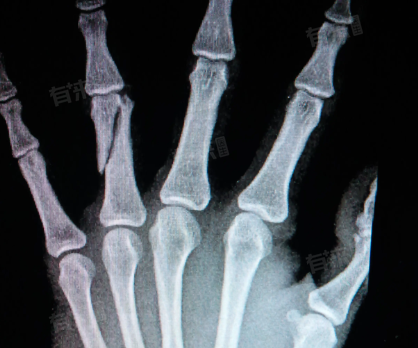

4、影像学检查:是确诊手指骨折的必要手段,X线片是最常用的检查方法,可以清晰地显示骨折的部位、类型和移位情况。对于细微的骨折或骨裂,可能还需要进行CT或MRI等进一步检查以明确诊断。